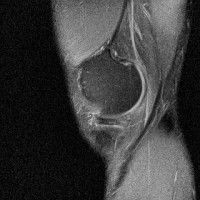

무릎 mri 간단히 봐주실 수 있으시나요 ㅠㅠ

안녕하세요 8년전 십자인대 수술하고 최근 무리한 운동에 무릎 불편감이 생겨서

mri 찍었습니다.

진단결과는 첫 찍은 병원에서 활액막염 이라는 진단을 받았습니다. 혹시 봐주실 수 있으실까요?

올라온 MRI가 단편적이라서 정확한 진단에 어려움이 있지만 십자인대에는 큰 이상이 있지는 않은것 같으며, 무릎관절내 물이 있는 것으로 보아 활액막염의 진단이 맞을 것 같습니다.

하지만 단편적인 영상이기 때문에 촬영병원에서 정확한 판독지 등을 받으시는 것이 좋겠습니다.